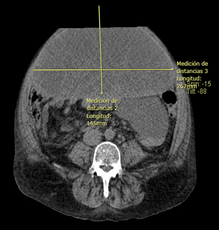

Se presenta el caso de un paciente masculino de 58 años de edad, originario y residente de la CDMX, ocupación chofer, toxicomanías: alcoholismo interrogado y negado, con antecedente de hipertensión arterial sistémica de 20 años de diagnóstico en tratamiento desde hace 6 meses con diurético de asa y ahorrador de potasio, diabetes tipo 2 de 22 años de diagnóstico en tratamiento con insulina glargina, enfermedad renal crónica en estadio KDIGO IV sin especificar tiempo de diagnóstico e hipotiroidismo primario de 5 años de diagnóstico en tratamiento con levotiroxina; sin antecedentes quirúrgicos. Quien ingresa a piso de medicina interna debido a proceso infeccioso de vías respiratorias, sin embargo llamaba la atención la importante distensión abdominal, que a la exploración física se encontraba con un abdomen globoso, con un perímetro de hasta 150 cm, peristalsis presente, no depresible, mate a la percusión, que condicionaba a la presencia de disnea, al interrogatorio dirigido el paciente comentó haber presentado aumento progresivo del perímetro abdominal desde hace 6 meses, ante lo cual había acudido con su médico familiar quien había instaurado manejo con diuréticos sin presentar mejoría y en su lugar continuaba con incremento del perímetro, negó síntomas acompañantes como nauseas, emesis, pérdida de peso, diaforesis nocturna; durante su estancia en servicio de medicina interna se decidió realizar paracentesis obteniendo una muestra de 500 cc de un líquido macroscópicamente color marrón, con el siguiente reporte de análisis citológico y citoquímico: hemoglobina 250, eritrocitos 400, leucocitos 0, tinción Gram con escasos cocos gram positivos, glucosa 67, albúmina 2, proteínas 4.8, dhl 447. Cultivo sin desarrollo bacteriano. Se realiza estudio ultrasonográfico abdominal con reporte de colecistitis crónica litiásica y cavidad abdominal con múltiples septos; por lo que se programa tomografía computada simple de abdomen con el siguiente reporte: Anterior a las asas intestinales y a órganos sólidos, se observa una imagen ovalada, de aspecto quístico, homogénea, que registra densidades de 1 a 11 UH, sugestiva de quiste mesentérico, con dimensiones máximas 272 mm x 145 mm x 267 mm (IMAGEN 1,2 y3). Hígado de forma, tamaño y situación habitual, bordes regulares, homogéneo con aspecto granular, sin lesiones ocupativas en su parénquima ni dilatación de la vía biliar. Bazo de forma y situación habitual, de dimensiones aumentadas, mide 143 mm en su eje mayor, con aspecto homogéneo. No se observa líquido libre en cavidad abdominal ni hueco pélvico.

IMAGEN 3: TAC simple abdominal: Corte axial, se observa una imagen ovoidea hipodensa con longitud mayor de 267mm.